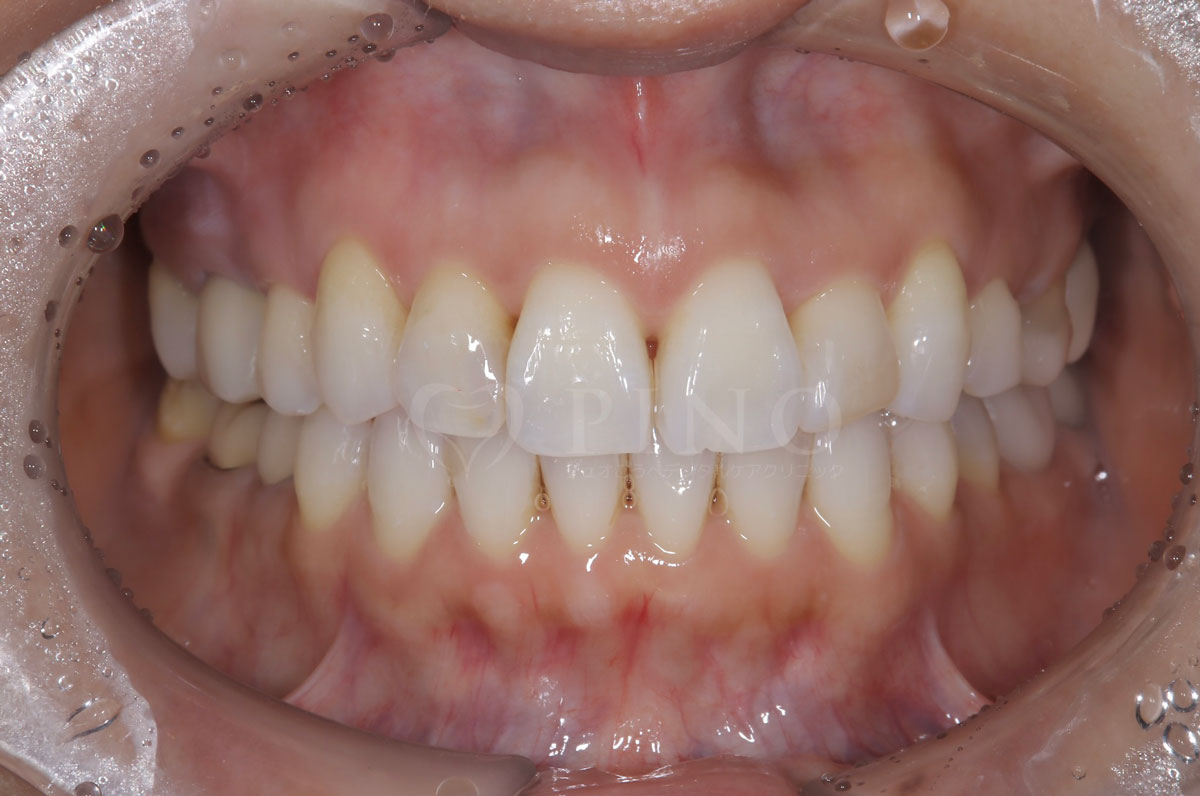

症例4:噛み合わせが深く、下の歯が見えないのが気になる(10代女性)

主訴 噛み合わせが深い、下の歯が見えない 診断名 過蓋咬合(かがいこうごう) 治療方法 マウスピース全顎矯正 抜歯 なし オルソパルス なし 治療期間 1年1ヶ月 費用 746,000円 副作用・注意点 矯正後の後戻りを防ぐためリテーナーの使用が必要となる -